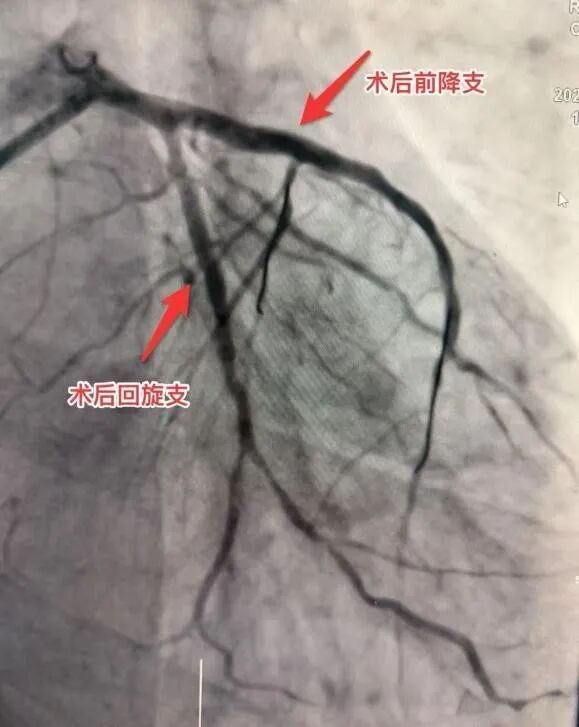

面对远超预期的结果,冠脉介入专家小组结合病情及心电图,审慎评估,由马江伟主任主导,为患者在前降支及左回旋支精准植入两枚支架。术后造影显示,血流恢复至理想的TIMI 3级,血运重建成功。